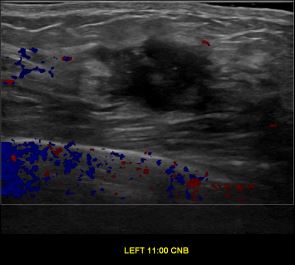

상기환자는 좌측 유방 만져지는 멍우리로 내원하신 30대중반 여성분으로 의심스러운 좌측혹 조직검사 시행해 유방암으로 진단되었습니다